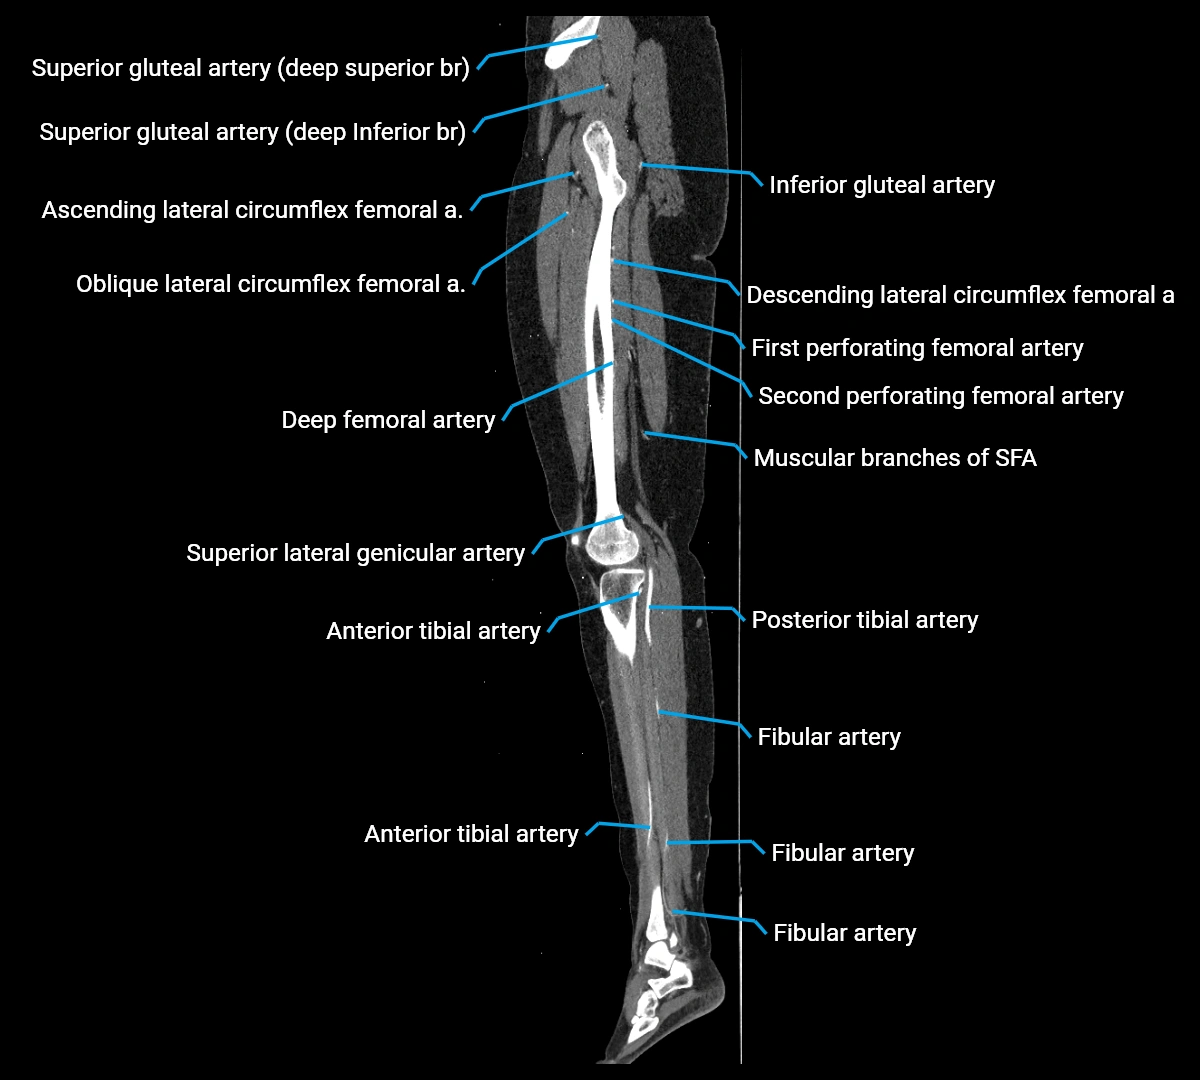

Contrast-enhanced CT (CTA):

• Gold standard for abdominal aortic imaging

• Provides excellent detail of lumen, wall, aneurysm, thrombus, and branch vessels

• Multiplanar and 3D reconstructions help in aneurysm measurement, stent graft planning, and dissection evaluation